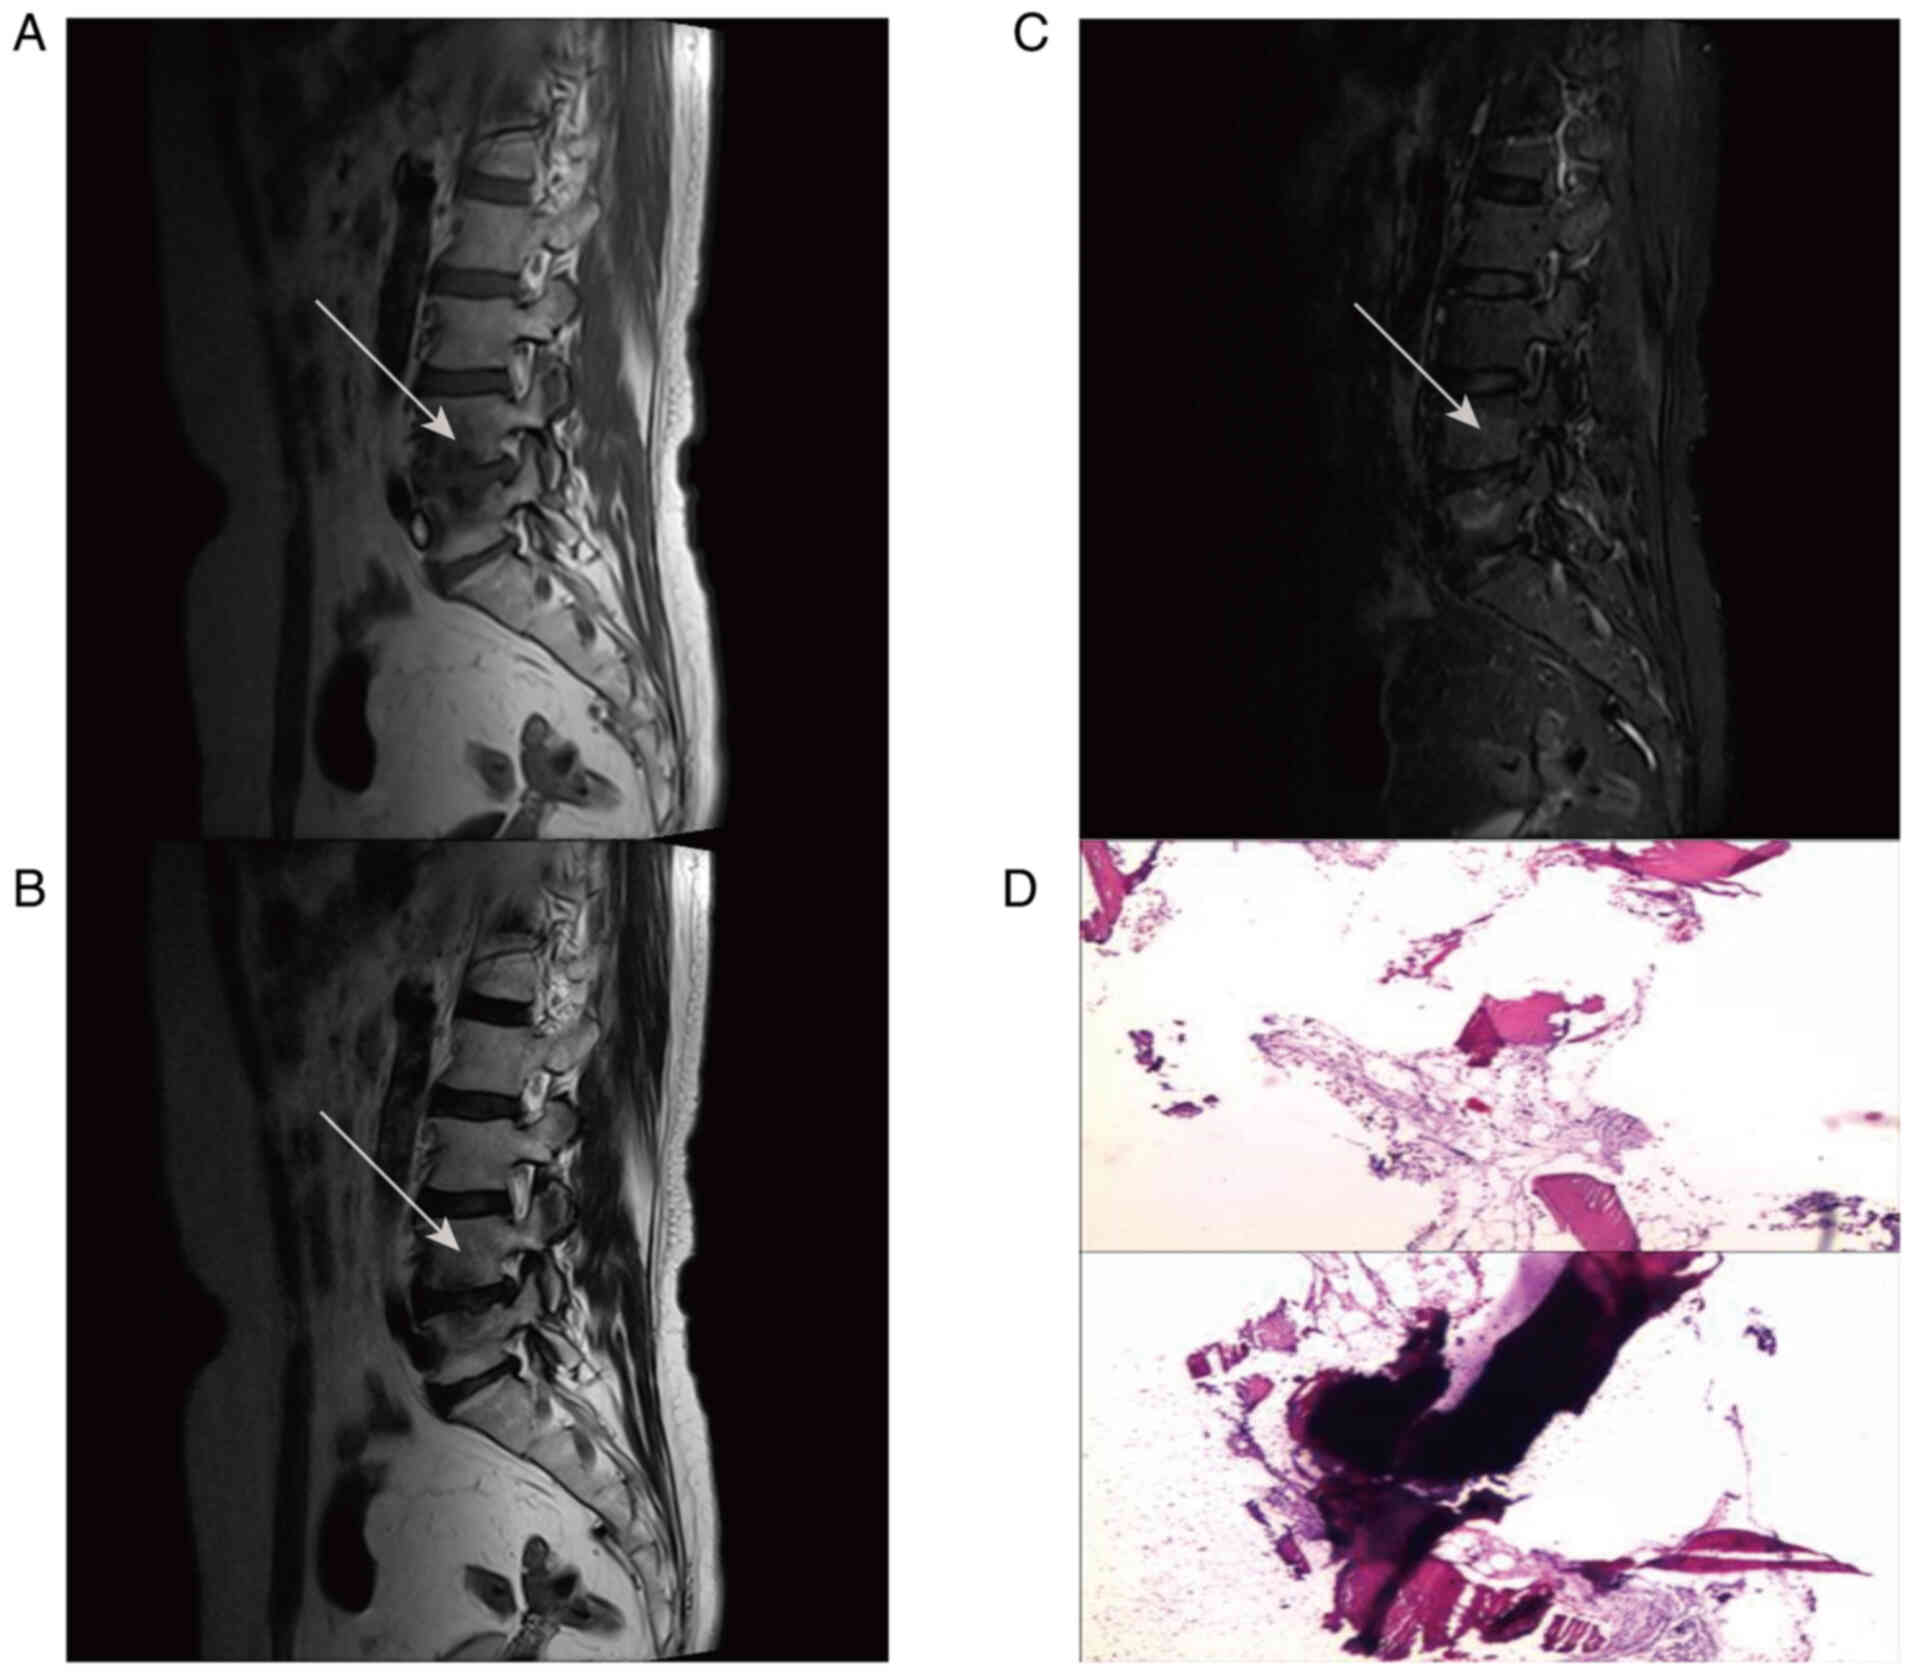

Figure 1

Figure 2

Figure 3

Figure 4

Figure 5